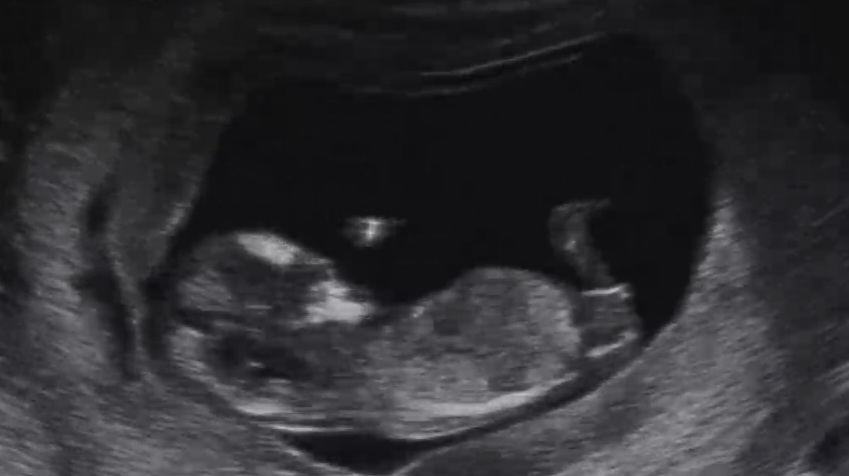

성별 뭐같은지 같이 봐주세요☺️

12주차 오늘 초음파 찍고 너무 궁금해서 여러 의견 듣고싶어서 글 써봅니다 ㅎㅎ 다른분들 투표는 많이 해봤는데 제 아기 성별 질문 올리니 긴장 되네요 ㅎㅎ